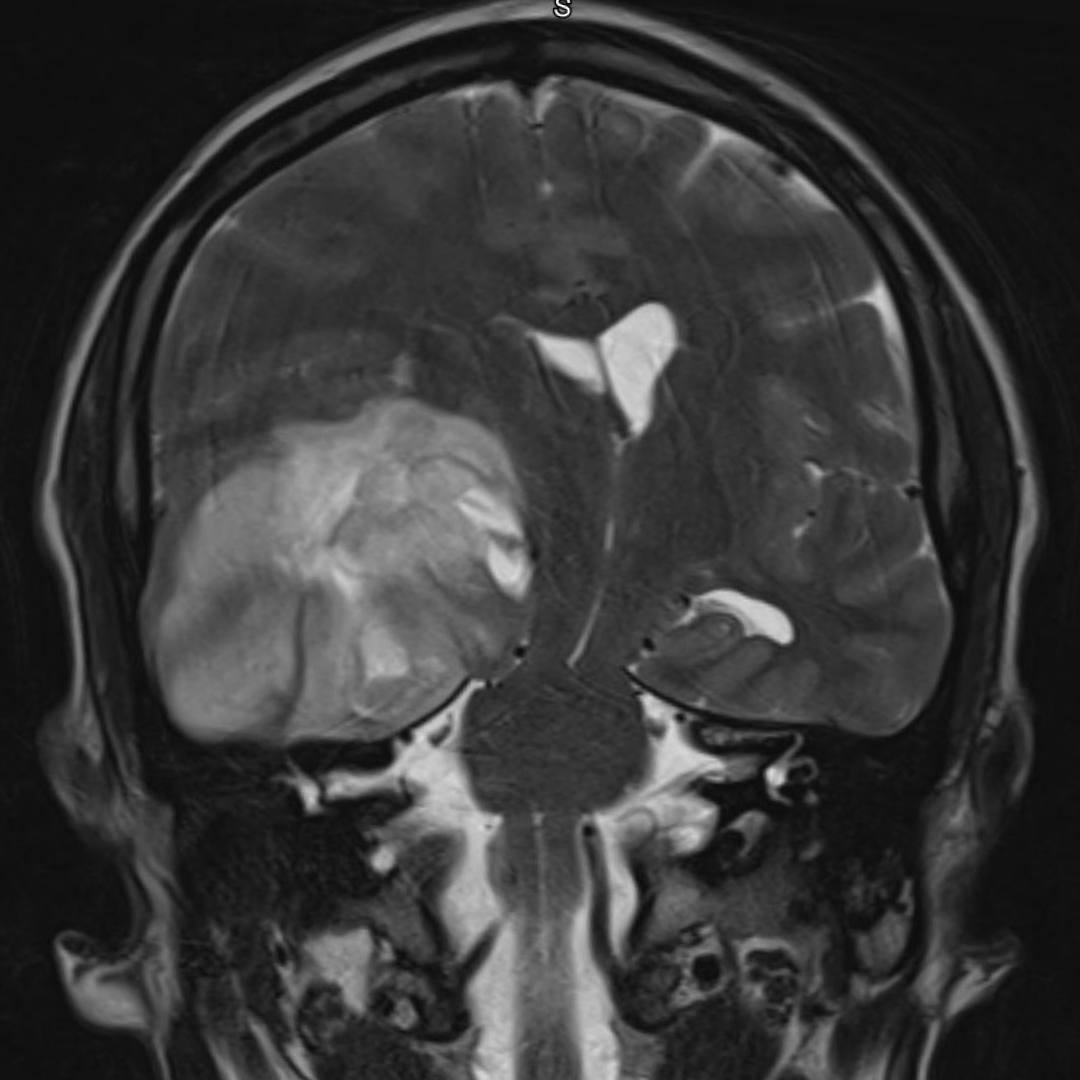

При проведении МРТ головного мозга выявлена опухоль правой височно-теменной области с переходом на островок, вовлечением базальных ядер справа и мозолистого тела с выраженным перифокальным отеком с дислокацией срединных структур мозга влево, компрессией правых бокового и третьего желудочков, среднего мозга.

При введении контрастного препарата визуализировался участок интенсивного кольцевидного накопления по периферии кистозного компонента опухоли.